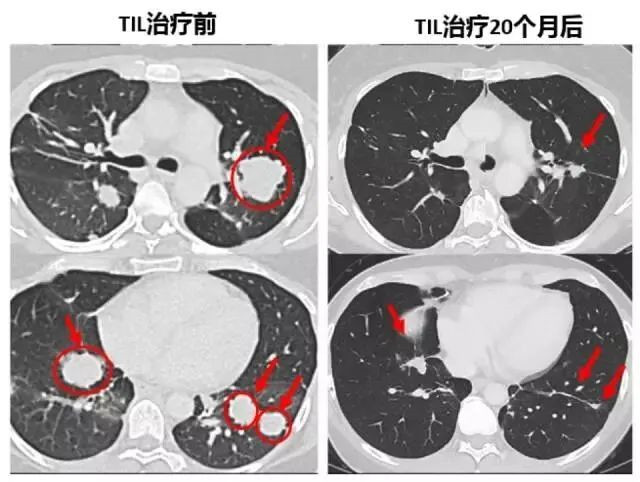

△ 治療前後的(de)CT與MRI對(duì)比圖,腫瘤明(míng)顯縮小(xiǎo&×σ)

下(xià)面的(de)對(duì)照(zhào)圖可( ™πkě)以非常明(míng)顯看(kàn)到(dào),第二次治療前肺部布滿的(de)腫©¶€&瘤,包括一(yī)些(xiē)個(gè)頭非φ ↕常大(dà)的(de),第二次TIL細胞治 ∑≈≠療20個(gè)月(yuè)後複查,這(zhè)些>★(xiē)腫瘤都(dōu)竟然都(dōu)明(míng)顯地(dì)縮€•δ小(xiǎo)了(le)。

△ 腫瘤明(míng)顯縮小(xiǎo)